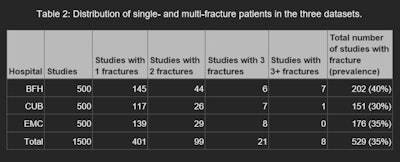

For each hospital, the authors created a dataset of 500 records of patients 21 and older of consecutively sampled radiographic exams for suspected traumatic fractures of the appendicular skeleton and/or pelvis. The data included all available images, clinical referral notes, and radiology reports for each of the exams, as well as reports for any MRI or CT imaging performed within two weeks of the initial radiographs. The anatomical sites included in the datasets were the shoulder, upper arm, forearm, elbow, wrist, hand, fingers, hip, pelvis, upper leg, lower leg, knee, ankle, and feet.

Statistical analysis was performed on both patients and fractures; performance metrics were calculated for each hospital’s data. A fracture was considered detected if there was an overlap between the reference standard and the AI software’s bounding box. Sensitivity fracture-wise (SEFW) was defined as the proportion of unique fractures correctly identified in at least one projection. specificity patient-wise (SPEPW) was defined as the proportion of patients with no fracture detected by the AI software in patients with no fracture according to the reference standard.

The researchers also calculated the average number of false-positive fractures per patient (FPPPFW). In order to assess the value of the tool for triage, they also calculated a triage-specific sensitivity measure (SEPW-triage) -- for example, the proportion of patients in whom at least one fracture was detected.